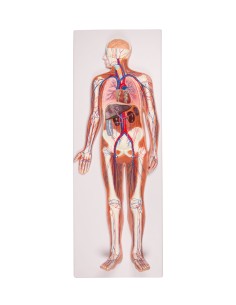

Dal cranio in 22 parti con incastri magnetici ai modelli di colonna vertebrale, da quelli di articolazioni a quelli di cuore, ogni pezzo della nostra collezione è progettato per un’immersione totale nello studio dell’anatomia umana. I nostri modelli, realizzati tramite scansioni di ossa vere, garantiscono un’esperienza tattile autentica e una fedeltà di peso quasi identica agli originali.

Essenziali per studenti e professionisti, i nostri modelli anatomici sono strumenti didattici che permettono di osservare le strutture anatomiche con precisione, eliminando la necessità di dissezioni o studi invasivi. Sono inoltre utili per spiegare ai pazienti le patologie, rendendo la comunicazione più efficace e risparmiando tempo prezioso.